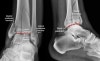

X-ray : 삼과 골절(Trimalleolar fracture)

삼과골절(trimalleolar fracture)은 뒤쪽 복사뼈 골절이 포함된 경우입니다. 발목의 뒤쪽탈구에서도 삼과골절이 동반될 수 있으며, 이런 경우를 '삼과골절-탈구'라고 합니다.